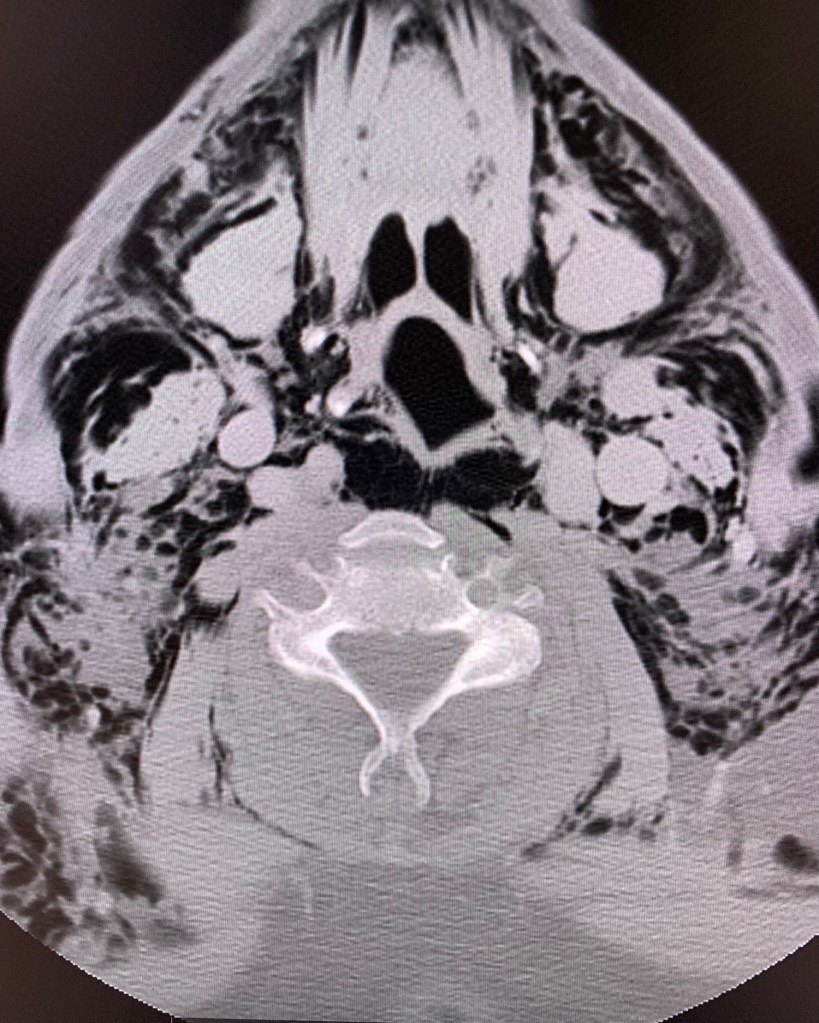

“Ghosting with Gas”

This ghoulish CT image resulted from subcutaneous and deep space neck emphysema (gas) dissecting upwards from the chest.